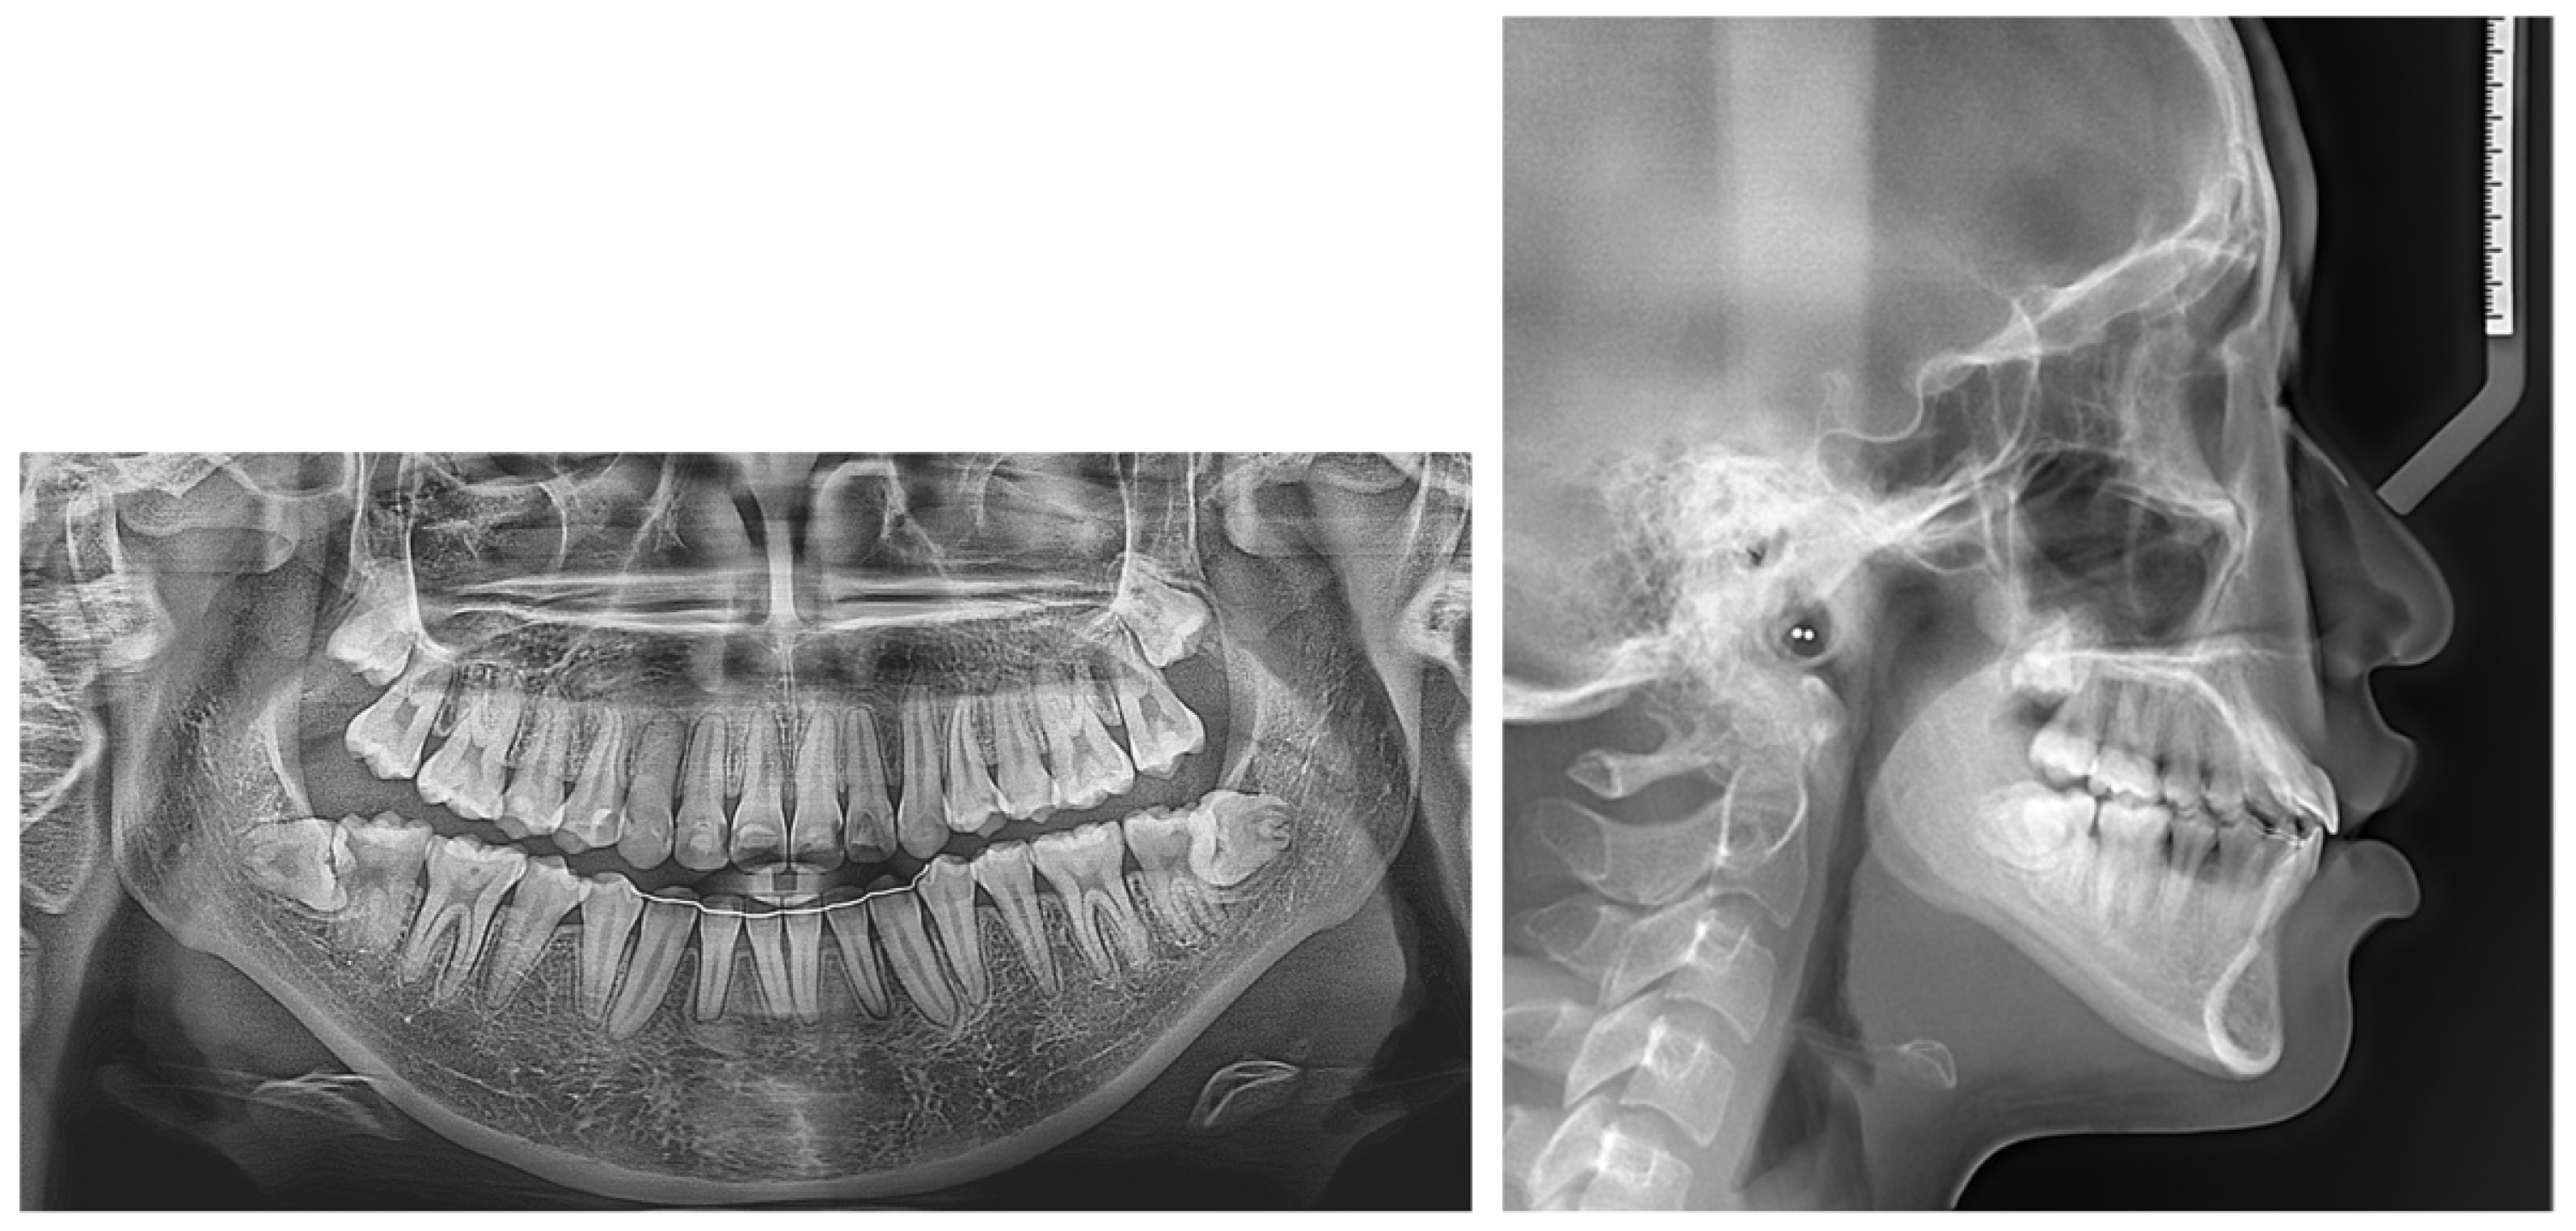

2.4. Treatment Progress

2.5. Treatment Results